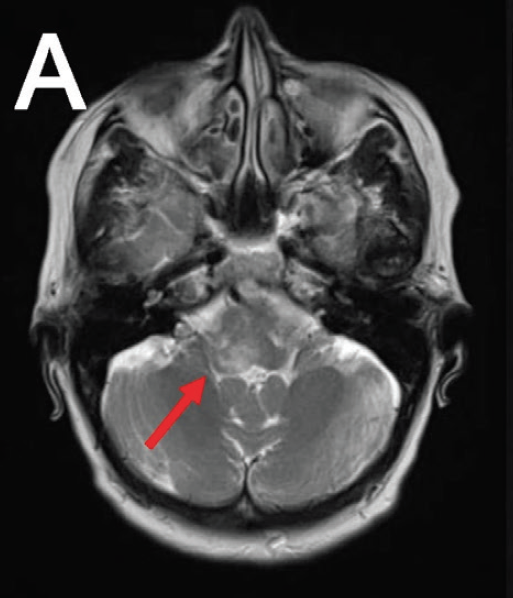

Aristides C.C. Avgeris, MD; Morgan C. Jordan, BA; Travis Dichoso, MS; Allison Baroco, MD; Atrac Kay, MD

Rhombencephalitis is a rare manifestation of infection with Listeria monocytogenes, developing in only 4.3% to 9% of cases of listerial infection with CNS involvement.